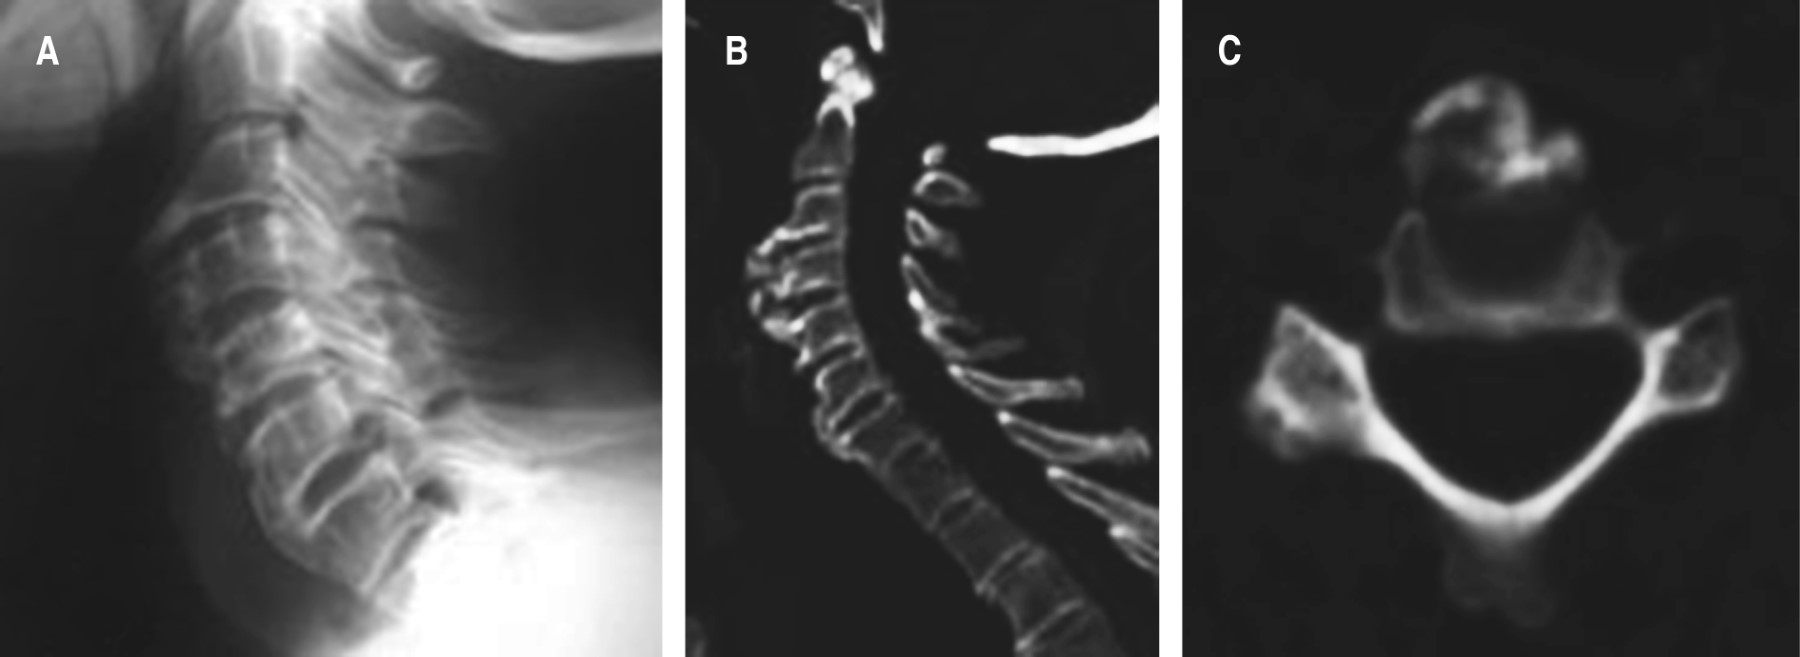

La videodeglución mostró una detención del contraste justo por encima del osteofito de C3, que se corresponde con la zona de la epiglotis, evidenciándose además que una escasa cantidad de contraste se dirigía a la vía aérea (Figura 2).

Figura 2